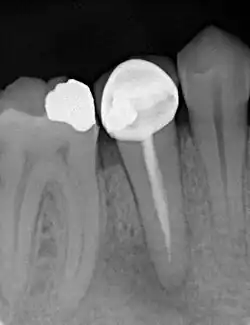

Anschließend wird eine ausreichend große Zugangskavität geschaffen und eventuell. vorhandene Wurzelstifte sowie das alte Wurzelfüllmaterial mit Spezialfeilen aus den Kanälen vollständig entfernt. Ganze Kanäle oder Kanalabschnitte, die bei der ersten Wurzelkanalbehandlung nicht behandelt wurden, werden zusammen mit den freigeräumten Kanälen auf ganze Länge bis zum natürlichen Ausgang an der Wurzelspitze aufbereitet. Ziel ist, die vollständige Durchgängigkeit der Kanäle zu erreichen. Im Kanalsystem verbliebene, abgebrochene Instrumentenfragmente aus der Erstbehandlung werden gegebenenfalls entfernt.[19]

Das Wurzelkanalsystem wird, wie nach einer Erstbehandlung, definitiv mit einem volumenbeständigen und biokompatiblen Füllmaterial, meist mit Guttapercha, (1) verschlossen.